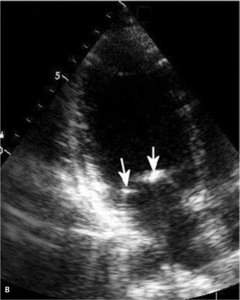

Toczeń rumieniowaty układowy

Zwiększone ryzyko zaburzeń zakrzepowo-zatorowych u chorych z toczniem rumieniowatym układowym wynika przede wszystkim z częstej obecności przeciwciał antyfosfolipidowych u tych chorych. W ostatnich badaniach wykazano, że zwiększone stężenie aCL i anty-ß2GPI w klasie IgG powodują wzrost ciśnienia skurczowego w prawej komorze (ryc. 3A, B) [11]. Stwierdzono także większą częstość występowania przeciwciał aCL u chorych z SLE i nadciśnieniem płucnym w porównaniu z chorymi z prawidłowym ciśnieniem w tętnicy płucnej [12]. W innym badaniu chorych z mieszaną chorobą tkanki łącznej (mixed connective tissue disease, MCTD) nadciśnienie płucne było związane ze zwiększonym stężeniem przeciwciał anty-ß2GPI [13]. Podwyższenie ciśnienia skurczowego w tętnicy płucnej związane z występowaniem przeciwciałami aCL może wynikać z mikrozakrzepicy lub mikrozatorowości, która zwiększa opory naczyń płucnych, powoduje wzrost ciśnienia skurczowego w prawej komorze i prowadzi do powiększenia prawej komory. Należy podkreślić, że względne ryzyko zatorowości płucnej u chorych z SLE w pierwszym roku od rozpoznania w porównaniu z populacją ogólną jest bardzo duże i wynosi 10,23 [14].